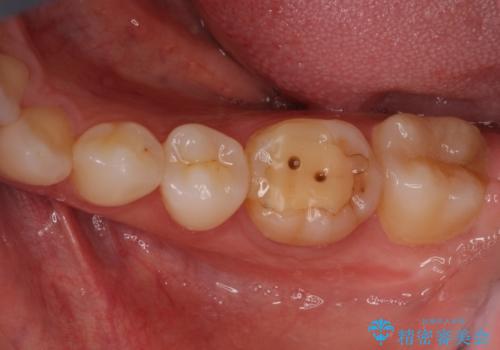

海外転勤が決まり、急いでセラミック治療をしてほしいとご来院された患者様です。

根管治療に症状がなく、上の歯に関しては土台もそのまま使用可能であったため、下の歯の土台、上下の歯のセラミック治療を行いました。